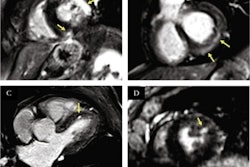

The astronauts' brains were imaged before and after the missions, with preflight MRIs performed a mean of 287.5 days before launch (range, 18-627 days) and postflight MRIs performed a mean of 6.7 days after spaceflight (range, 1-20 days). The researchers also paired preflight and postflight MRI cine clips generated from a subgroup of astronauts who had high-resolution MRI scans -- 12 who underwent long-duration flights and six who underwent short-duration flights -- to evaluate the extent of the narrowing of CSF spaces and displacement of brain structures.

Among the 18 astronauts who undertook long missions, 17 experienced narrowing of the central sulcus (94%), while only three of the 16 astronauts who had short missions experienced this narrowing (19%), Roberts and colleagues found. Cine clips showed an upward shift of the brain after all long-duration flights (12 astronauts) and in one of six astronauts after short-duration flights. In addition, three of these 12 astronauts had optic disk edema (also called vision impairment and intracranial pressure syndrome, or VIIP) and a narrowing of the central sulcus.

MRI cine clip shows evidence of an upward shift of the brain and narrowing of cerebrospinal spaces at the top of the brain in a NASA astronaut stationed aboard the International Space Station. Courtesy of MUSC.